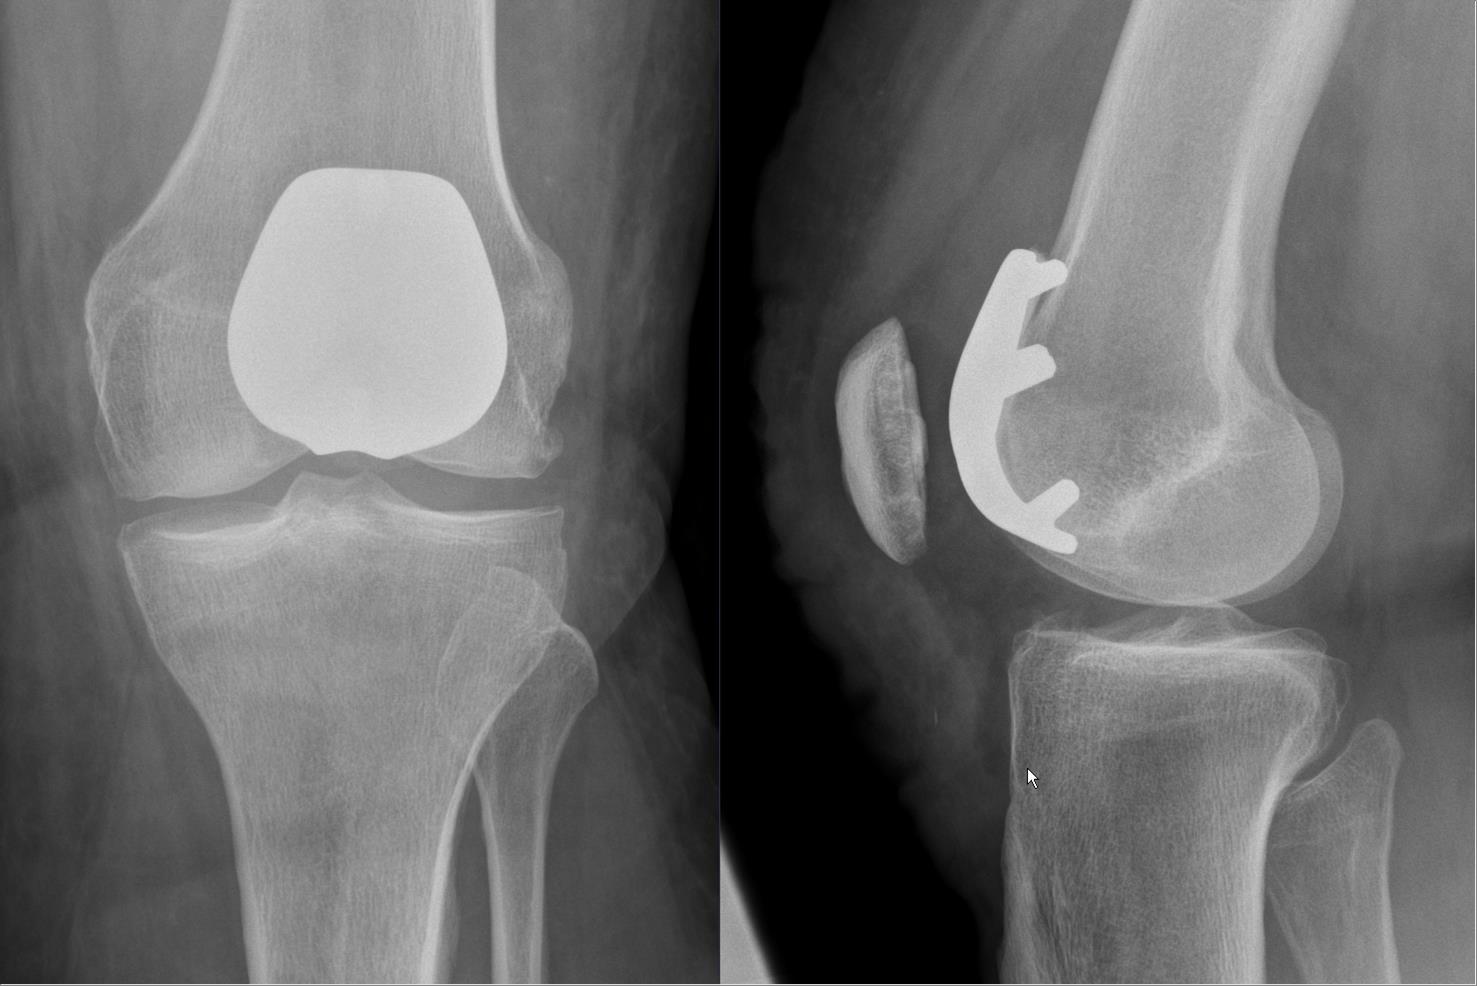

Plain radiograph of a human knee joint showing the femur, tibia, and patella.

Lateral radiograph of a retropatellar knee joint prosthesis.